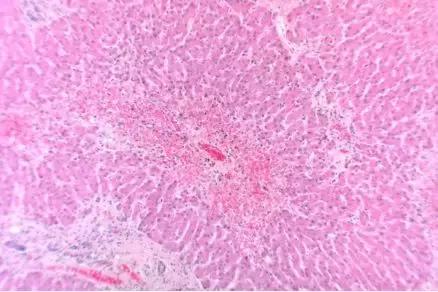

血液中的凝血酶

在显微外科、包括整形和重建手术后有一种棘手的并发症——“静脉淤血 ” 。手术中的血管被切割后可不会意识到自己会被人工缝合好,为了避免人体失血过多,血管内壁会释放凝血物质,导致术后会出现静脉血管血流受阻或淤积的情况。

一旦没有形成有效的静脉回流,手术的器官就会出现淤紫和肿胀继而坏死。如果想真正让血液流通起来,重建血液循环是最关键的步骤。